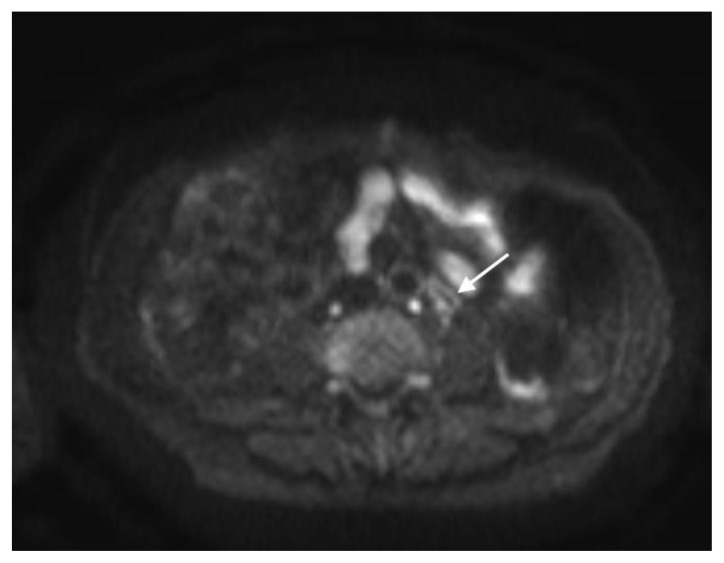

Figure 10.

78 year-old male with IgG4-related autoimmune disease.

Findings: DWI MRI demonstrates hyperintense soft tissue surrounding the SMA (solid arrow). Also note regions of hyperintensity throughout the renal parenchyma (dashed arrow).

Technique: Axial DWI-weighted (1.5T, TR 1372, TE 62.5, slice spacing 6.6)

The MRI revealed soft tissue encased the proximal common bile duct (CBD) and biliary hilum, resulting in a 4cm-long stricture, with increased upstream intrahepatic biliary dilatation (Figures 5, 6). The hepatic parenchyma demonstrated diffuse heterogeneous enhancement, without a focal mass or pseudotumor, consistent with inflammatory changes. The pancreas demonstrated parenchymal T2 hyperintensity and T1 hypointensity with diffuse enhancement, including an enhancing peripheral soft tissue rind, again consistent with autoimmune pancreatitis (Figure 7). The kidneys also demonstrated multifocal regions of abnormal enhancement and restricted diffusion (Figure 9, 10). Persistent enhancing soft tissue surrounding the SMA and IMA was again noted (Figure 11, 12).